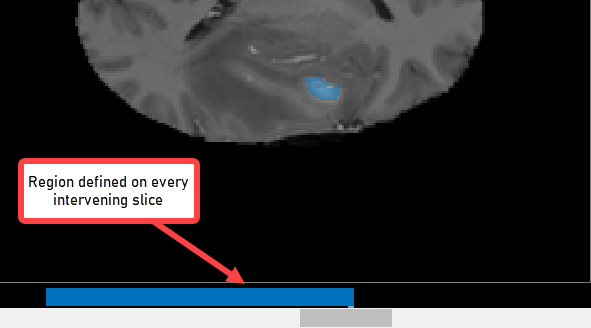

With the object defined on two slices, click Auto Interpolate. The app automatically defines the ROI on all the intervening slides. The app uses blue bars to indicate all the slices that have ROIs, which now appear as a solid bar from slice 35 to slice 88.

CreateBinaryMaskUsingVolumeSegmenterExample_07.png